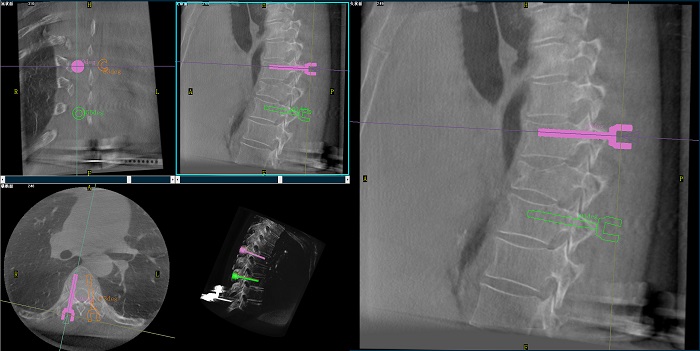

②機(jī)器人輔助胸椎手術(shù)操作難點(diǎn)之路徑規(guī)劃

人體胸椎的椎弓根較腰椎更狹窄,周圍有重要的神經(jīng)和血管,選擇合適尺寸和長度的螺釘至關(guān)重要。螺釘過粗可能損傷椎弓根,過細(xì)容易發(fā)生形變,固定強(qiáng)度不夠;螺釘過長可能穿透椎體前緣,造成損傷,過短則固定不牢。

普愛醫(yī)療手術(shù)導(dǎo)航定位系統(tǒng)解決方案

使用機(jī)器人輔助手術(shù),醫(yī)生不僅可以在影像的引導(dǎo)下,一次性完成多枚螺釘?shù)穆窂揭?guī)劃,提高手術(shù)效率,而且可以精確地選擇螺釘?shù)慕嵌取⒅睆胶烷L度,提高手術(shù)的成功率。